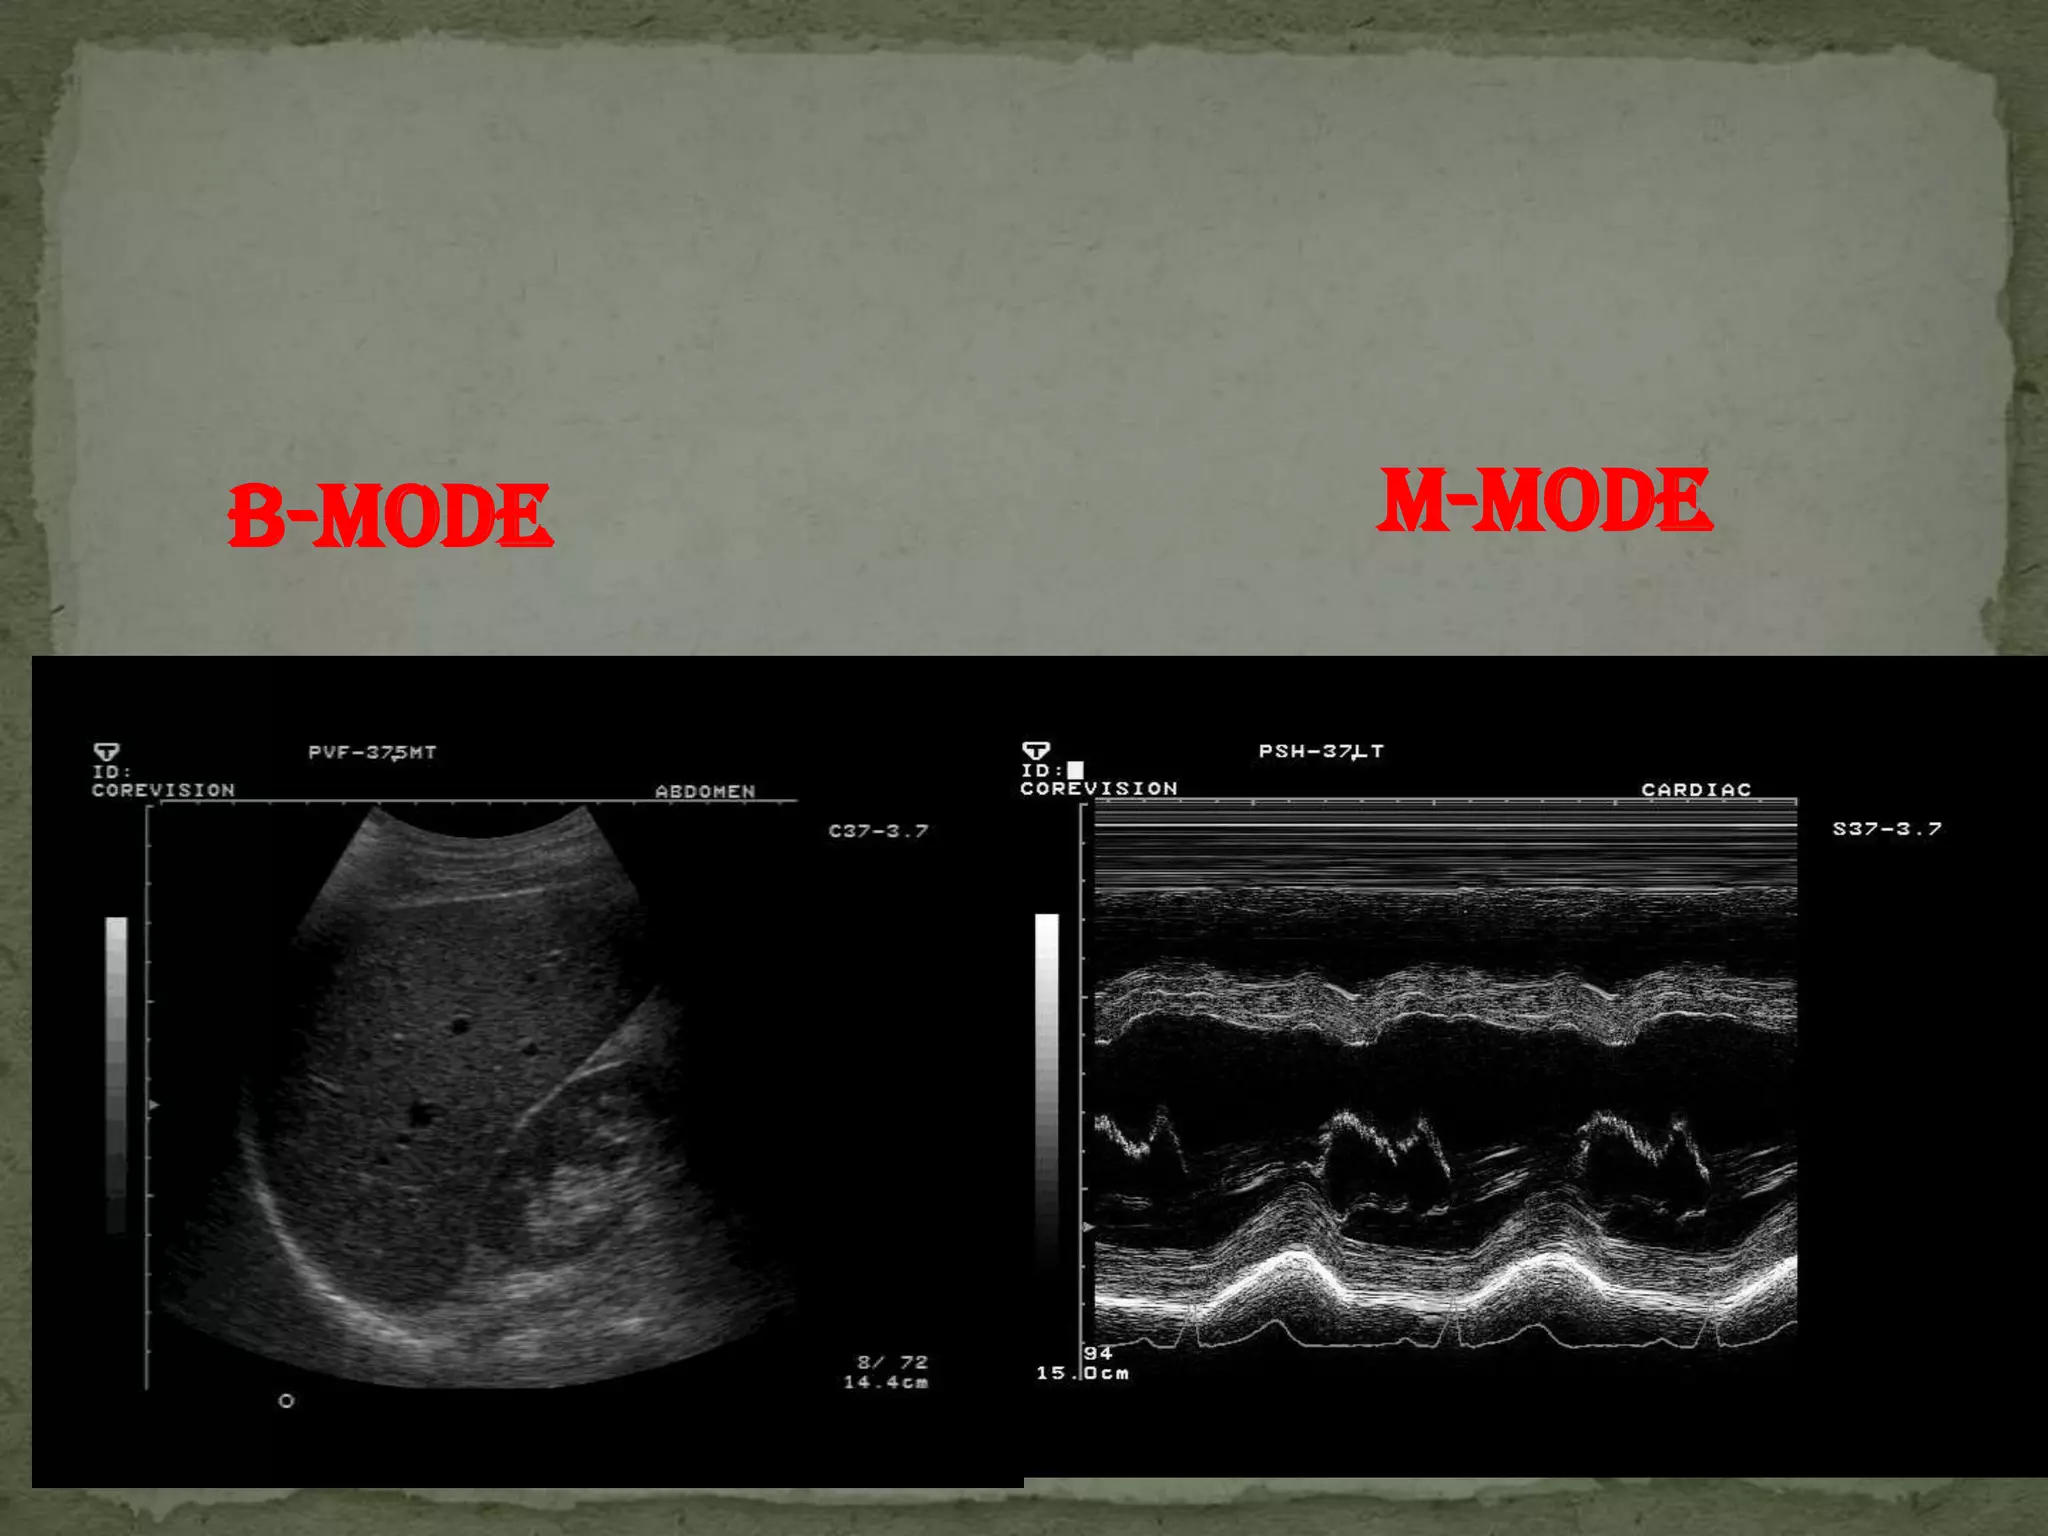

B-MODE   M-MODE